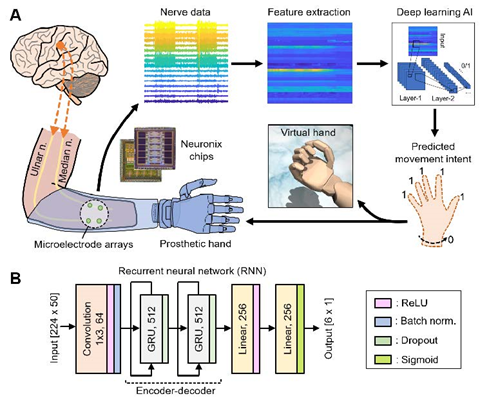

人工智能神经解码器和信号处理范式。

通过Neuronix神经接口芯片从受试者的截肢手臂上获取神经数据,随后进行特征提取,然后,深度学习AI使用特征数据来预测受试者同时移动几个自由度的意图。预测结果被实时映射到虚拟手或假手的运动中 (B)基于递归神经网络(RNN)架构的深度学习AI系统的设计。

研究使用了基于递归神经网络(RNN)架构的AI体解码运动意图,实验中AI算法可以同时解码受试者六个自由度的运动意图,包括单个手指弯曲和腕旋前。通过这种设置,用户只需想一想他们希望假手做出的动作,大脑将命令信号发送到连接点的神经,接口检测到这些信号,通过AI体解码,相应的命令发送到人工肢体,后者成功执行大脑的指令。